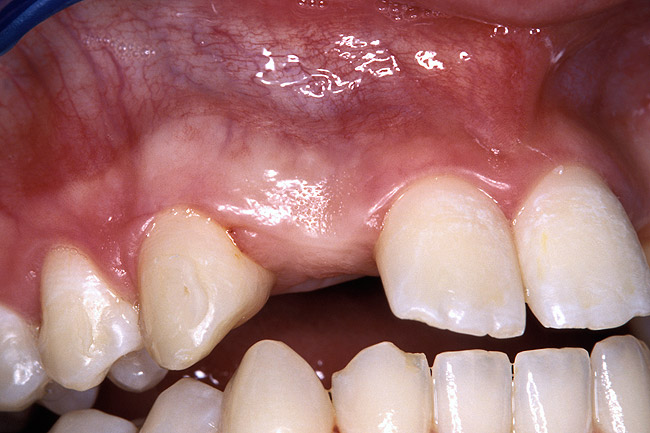

Periapical radiographs were taken to help determine the mesial-distal inclinations of the adjacent tooth roots (Figure 1). The radiographs revealed a serious issue, convergent roots for the right canine and right central, which eliminated that area as a potential implant-receptor site. The space between the left central and canine teeth was minimal, although the roots were relatively parallel. Clinical examination (manual palpation of the root eminences superiorly to the vestibule on the right side) confirmed the root convergence (Figure 2A). The flat, wide zone of the keratinized tissue and lack of interdental papilla was evident for the missing right lateral incisor. There was a marked difference in clinical appearance for the left lateral, which could impact the eventual plan of treatment (Figure 2B). Other significant clinical findings included bilateral facial bone concavities, which existed as a result of the congenitally missing tooth roots. As a diagnostic cue to the underlying bone topography, it is important to follow the demarcation between attached and unattached gingival tissue, and note the crestal width of the available keratinized tissue (Figure 2C).

Figure 2c  Pretreatment buccal views showed (A) root convergence, (B) a difference in clinical appearance of the left lateral, and (C) significant crestal width of keratinized tissue.

Figure 2c